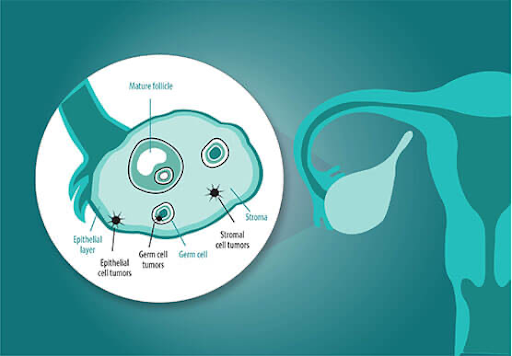

There are several main types of ovarian cancer:

● Epithelial tumors: These start in the outer surface of the ovary and are the most common type.

● Germ cell tumors: These begin in the egg-producing cells and are more common in younger women.

● Stromal tumors: These develop in the hormone-producing cells of the ovary and are less common.

There are several main types of ovarian cancer:

● Epithelial tumors: These start in the outer surface of the ovary and are the most common type.

● Germ cell tumors: These begin in the egg-producing cells and are more common in younger women.

● Stromal tumors: These develop in the hormone-producing cells of the ovary and are less common.